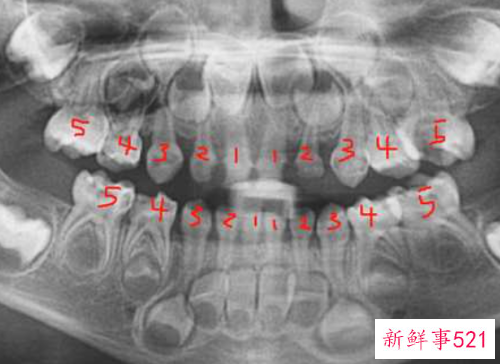

乳牙两岁半长齐,共20颗。(下图为三岁全景片:左右各五颗,上下各十颗)